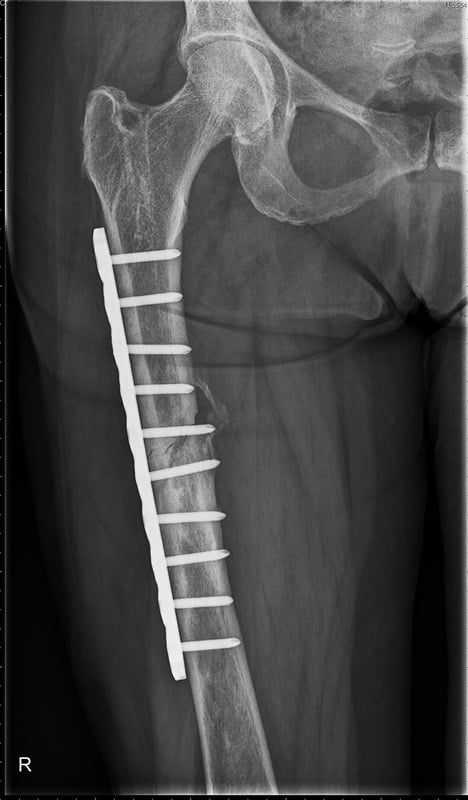

• Εσωτερική Σταθεροποίηση (Οστεοσύνθεση): Αυτή η μέθοδος περιλαμβάνει την τοποθέτηση μεταλλικών πλακών, βιδών ή ράβδων για να

σταθεροποιηθεί το κάταγμα εσωτερικά. Η ακριβής ευθυγράμμιση των οστών επιτρέπει την ταχύτερη και πιο σταθερή επούλωση.